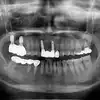

Before

임플란트 수술받았는데 안아프게 잘해주시고 원장님과 선생님들 모두 너무 친절하게 해주셔서 좋았습니다 수술비도 너무 가성비가 굿인거 갔습니다 매우 만족합니다

김**

2024-07-05